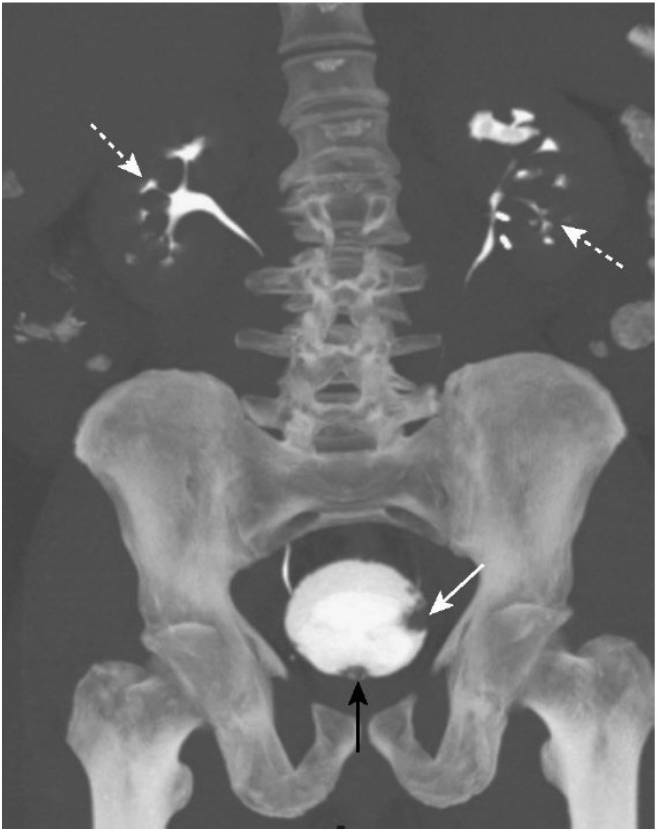

Рак таза у мужчин

Рак таза у мужчин 112 фото